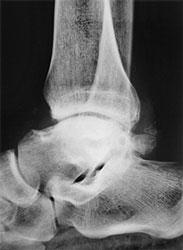

- Рентгенография. Самый важный диагностический параметр. Позволяет увидеть характерные неанатомические разрастания, имеющие вид шипов, крючков.

рентген голеностопного сустава. - КТ. Метод, позволяющий понять строение остеофитов. Также он помогает обнаружить патологию на начальной стадии, когда рентгена может быть недостаточно для постановки диагноза.

- Применяется для диагностики остеофитов в области голеностопного сустава, за исключением спорных случаев.

МРТ голеностопного сустава.